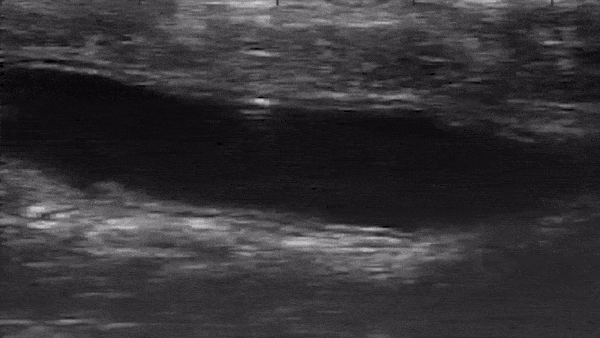

The team was able to demonstrate its robot in the colons of mice placed under anesthesia, with the tiny machine coated in mock drugs and inserted via the rectum inside a saline solution. The robot is made from polymer and metal and needs no battery or power source, instead being powered and controlled with magnetic fields from outside the body, with the scientists using ultrasound equipment to observe its movement. These results were also replicated in colons removed from pigs, which the team notes have similar characteristics to humans.